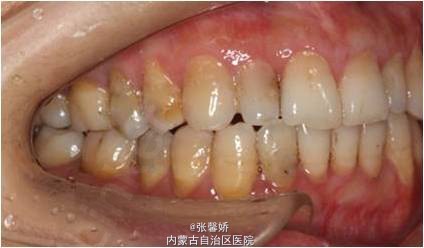

诊断 处理

牙列中度拥挤;A2、D4反合 处理:时代天使隐形矫治器矫治 拔除C8、D8 适当下前牙邻面去釉 排齐整平上下牙列,改正A2、D4反合 治疗时间2年左右,矫治后牙齿排列整齐,咬合关系良好,患者满意。

一年后随访,患者咬合关系仍稳定,尖窝锁结良好。 隐形矫治适应证的选择很重要,适合中低难度的成人病例,患者的配合和依从性要求较高。 此患者术前全景片可见多个充填物,为龋易感患者,而且牙周也不是很好,隐形矫治没有拖槽更利于患者口腔卫生的维护,防止龋病的发生和牙周病的加重。